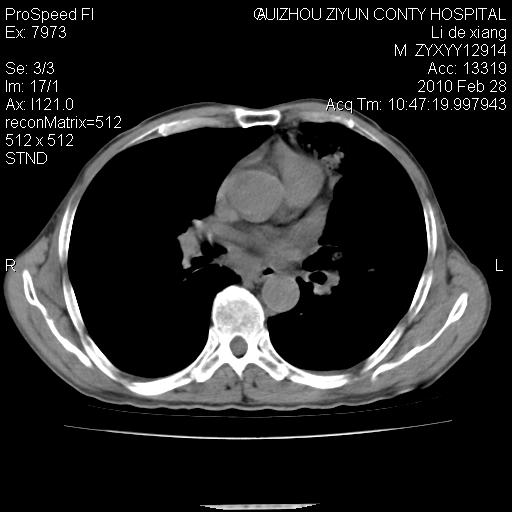

标题: CT24776:男 71Y 咳嗽咳痰胸痛两月,伴声音嘶哑。 [打印本页]

标题: CT24776:男 71Y 咳嗽咳痰胸痛两月,伴声音嘶哑。

左侧中央型肺癌伴左肺上叶阻塞性肺炎及节段性不张可能性大,建议纤支镜检查!

左侧中央型肺癌伴左肺上叶阻塞性肺炎及节段性不张可能性大,建议纤支镜检查!纵隔淋巴结转移.

左侧中央型肺癌伴左肺上叶阻塞性肺炎及纵隔淋巴结转移。

左肺门部肿块,伴左上肺斑块影,周边模糊,支持左肺中央型肺癌伴节段性不张及阻塞性肺炎,结合支气管镜检查。

患者有声音嘶哑,若时间长了,没改变,喉镜检查无异常,可考虑左侧喉返神经受累,因为:左侧喉返神经绕主动脉弓或肺动脉韧带的主动脉端,沿气管与食管之间的沟上行至颈部.

支持肺癌.

左上叶支气管狭窄,阻塞性病变,肺门肿块,纵隔及肺门淋巴结增大,中央性肺癌

左肺中央型肺癌并阻塞性改变、纵膈 淋巴结转移

左侧中央型肺癌伴左肺上叶阻塞性肺炎及纵隔淋巴结转移

支持 左肺中央型肺癌伴左肺上叶阻塞性肺炎,纵隔淋巴结转移。